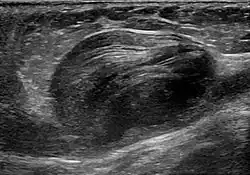

Abdominal aortic aneurysm involves a regional dilation of the aorta and is diagnosed using ultrasonography, computed tomography, or magnetic resonance imaging. A segment of the aorta that is found to be greater than 50% larger than that of a healthy individual of the same sex and age is considered aneurysmal.[9] Abdominal aneurysms are usually asymptomatic but in rare cases can cause lower back pain or lower limb ischemia.